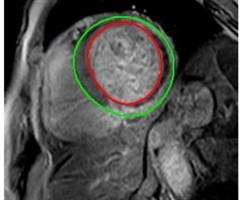

摘要目的:通过心脏磁共振(CMR)定量评估直接冠状动脉介入术(PCI)围术期使用麝香通心滴丸改善ST段抬高型心肌梗死(STEMI)病人冠状动脉微循环及增加存活心肌的效果。方法:本研究为多中心、随机对照、非双盲干预性的临床研究。入选拟进行直接...